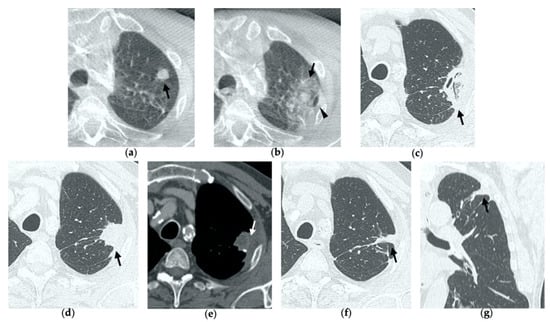

Figure 3. 63-year-old woman with pulmonary metastasis from colorectal cancer (CRC) in the right upper lobe. (a) Axial CT of the metastasis (black arrow) prior to treatment. (b) Cone-beam CT image obtained post-procedure shows hazy GGO (black arrow) of the ablation site surrounding the treated nodule. (c,d) Axial 2-month follow-up CT images show a large consolidation with hypoattenuating bubbles (black arrow) and no contrast uptake (white arrow). (e,f) Axial 5-month follow-up CT images demonstrate a decrease in the size of the consolidation (black arrow) with no central contrast enhancement (white arrow). (g,h) Axial CT images obtained after 8 months show minimal further decrease in size with no signs of residual disease.

Figure 4. 63-year-old-woman (same patient in Figure 3) with pulmonary metastasis from CRC in the right upper lobe. (a) Axial CT before treatment (black arrow). (b) Cone-beam CT image obtained at the end of the procedure shows GGO (black arrow) around the treated lesion. (c,d) Axial 2-month follow-up CT images show an elongated consolidation with hypoattenuating bubbles (black arrow) and no contrast uptake (white arrow). (e,f) Axial 5-month follow-up CT images demonstrate a tiny nodular uptake of contrast on the posterior margin of the consolidation (white arrow), suggestive of residual disease. (g,h) On axial CT images after 8 months the nodular enhancement persists (white arrow). (i) PET/CT image at 9 months proves residual disease on the treated lesion (white arrow) as well as simultaneous metastasis (white arrowhead) in the posterior segment.

3.2. Contrast-Enhanced CT at 1 Month

By the first month after MWA, the rim of parenchymal GGO has dissolved in most patients as a result of regressing parenchymal edema, inflammation and hemorrhage, and the ablation site appears as an area of consolidation with a mean diameter still larger than the preablation zone (Figure 3c,d and Figure 4c,d) [21]. It is, therefore, crucial in this phase to measure the area of consolidation by its maximum axial diameter in order to thoroughly compare it during the following phases [7]. The consolidation may demonstrate inner cavitation or a central hypoattenuating area with reduction in contrast material uptake, along with a mild peripheral enhancement layer as an expression of reactive hyperemia, which should present smooth with linear margins (Figure 1c) [7,15]. This phenomenon must be referred to benign periablational enhancement and it should be differentiated from pathological contrast uptake, which is usually more irregular and nodular-shaped [7]. It is, therefore, pivotal to perform CT before and after contrast material administration in order to adequately evaluate the enhancement features of the treated tumor. The ablation site may also show hypoattenuating bubbles or a cavity with thin walls, containing solid tissue with reduced contrast enhancement, necrotic material or air-fluid levels, and a communication between the cavitation and a bronchus may be recognized (Figure 2c–e) [7,16]. The latter being a common finding since the necrotic tissue may be evacuated through a bronchus and it should not be mistaken for rare although possible complications, such as an abscess or a broncho-pleural fistula (BPF). Unlike the normal cavitary changes of the ablation area, an abscess is a rare complication (0.5%) [20] and appears as a cavity with thick walls, irregular internal contours and air-fluid level, and must be suspected when fever and laboratory signs of infection are present [22]. Pleural changes are also common findings, especially in peripheral lesions, including pleural thickening in the region of pleura traversed by the microwave antenna, pleural retraction and effusion [15]. Reactive mediastinal lymphadenopathy often occurs at an early stage, and it should not be considered a sign of tumor progression [7,23].

4. Residual or Recurrent Disease

During follow-up, there are several evolution patterns of the ablation site, which should promptly raise the suspicion of incomplete ablation or local recurrence.

At the 1-month follow-up, incomplete ablation should be suspected if there is no increase in size of the ablation zone or if the consolidation demonstrates nodular enhancement akin to the original tumor [7,8].

At 6 months, any growth in size of the ablation area is suggestive of recurrence [7].

At all stages of follow-up, the appearance of either central or peripheral nodular or irregular enhancement should be considered as residual or recurrent disease (Figure 4f and Figure 5f), since the ablated area undergoes fibrous transformation, and it should not show contrast enhancement, except for the persisting peripheral safe zone [7,15].